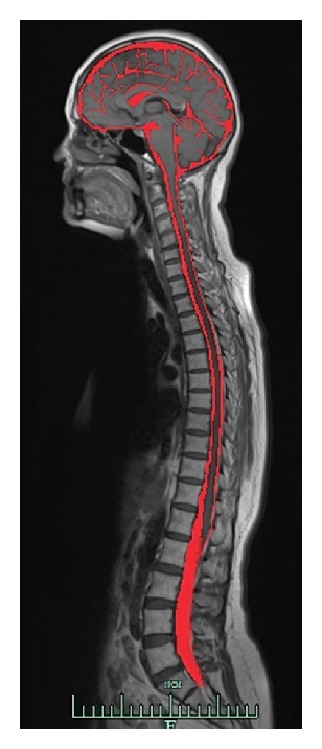

作者分析了发现脑脊液的历史、漫长和曲折之路。至少有35位医生和解剖学家在文中描述了这种生物流体存在的基本认识。在重要的解剖学、实验和临床工作的基础上,有四位最伟大的医生应该被认为是脑脊液的发现者:埃及的伊姆霍特普、威尼斯的尼科洛·马萨、意大利的多梅尼科·费利斯·科图尼奥和法国的弗朗索瓦·马根迪。

The author analyzes a historical, long, and tortuous way to discover the cerebrospinal fluid. At least 35 physicians and anatomists described in the text have laid the fundamentals of recognition of this biological fluid's presence. On the basis of crucial anatomical, experimental, and clinical works there are four greatest physicians who should be considered as equal cerebrospinal fluid's discoverers: Egyptian Imhotep, Venetian Nicolo Massa, Italian Domenico Felice Cotugno, and French François Magendie.